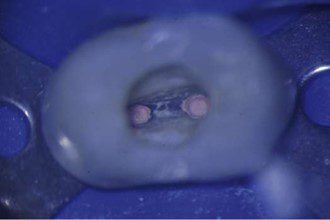

- Chụp X-quang thử côn chính: Hầu hết các bác sĩ chọn chụp X-quang sau khi côn chính được đặt vào ống tủy. Mục đích của “phim X-quang thử côn chính” là kiểm tra xem gutta-percha đã được đặt đúng đến chiều dài làm việc mong muốn hay chưa.

Ngoài ra, bác sĩ có thể chọn thêm một đến hai côn phụ trước khi chụp X-quang. Phim X-quang “lèn ban đầu” này được sử dụng để kiểm tra chiều dài côn gutta-percha chính đảm bảo không bị xê dịch trong quá trình lèn ban đầu, và không có khoảng trống ở 1/3 chóp ống tủy.

Nếu phát hiện lỗi trên phim X-quang côn chính hoặc lèn ban đầu, vẫn có thể dễ dàng rút côn ra khỏi ống tủy trước khi cắt bỏ, và sửa lại hoặc chọn côn chính mới. Rút côn ra khỏi ống tủy một cách chậm rãi.

- Tiếp tục lèn ngang: Nếu phim X-quang côn chính hoặc lèn ban đầu đạt yêu cầu, quá trình lèn ngang sẽ được tiếp tục. Cây lèn được đưa vào, và các côn phụ tiếp theo cũng được bôi sealer trám bít trước khi đặt vào ống tủy (hình 14.19).

Khi thêm nhiều côn phụ, cây lèn sẽ đặt vào ống tủy càng ít sâu hơn. Quá trình lèn nên tiếp tục cho đến khi cây lèn không thể đặt sâu hơn khoảng 4 mm dưới mức miệng ống tủy (hình 14.20).

- Cắt bỏ côn gutta-percha: Khi đạt đến mức trám bít phù hợp, các côn gutta-percha được cắt bỏ ở mức mong muốn. Có thể sử dụng cây nhồi nhiệt để cắt côn (hình 14.21).

Trong lịch sử, đèn Bunsen hoặc đèn cồn với cây nhồi tay được sử dụng nếu không có cây nhồi nhiệt điện. Cây nhồi nguội cầm tay được sử dụng để nén phần gutta-percha còn lại theo chiều dọc, lấp đầy bất kỳ khoảng trống nào ở vùng thân răng và tạo bề mặt gutta-percha mịn ở phần thân ống tủy (hình 14.22).

Nếu có đặt vật liệu bít miệng ống tủy, mức gutta-percha mong muốn là 1 đến 2 mm dưới mức đường nối men-xi măng mặt ngoài (CEJ) hoặc sàn tủy (ở răng cối lớn). Khoảng trống 1 đến 2 mm sau đó được lấp đầy bằng vật liệu bít miệng ống tủy. Nếu không đặt vật liệu bít miệng ống tủy, gutta-percha được nhồi đến mức đường nối men-xi măng mặt ngoài hoặc sàn tủy. Nếu cần khoảng trống để đặt chốt, có thể loại bỏ thêm gutta-percha đến mức phù hợp cho khoảng trống chốt.